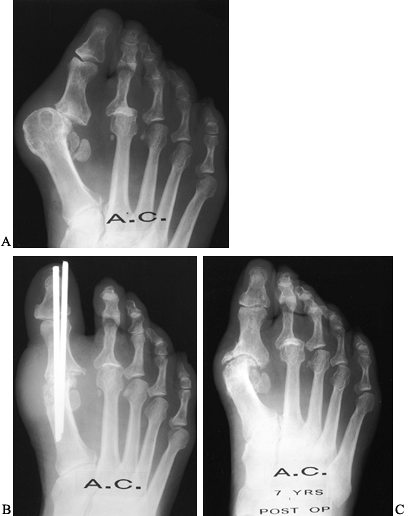

As progressive clawing of the lesser toes develops, little stability is

of weight is borne beneath the lesser metatarsal heads (Fig. 117.3).

![]() |

Figure 117.3. A: A typical rheumatoid foot showing severe hallux valgus and overlapping and clawed lesser toes. B:

The plantar surface of a foot, demonstrating prominent metatarsal heads, distal migration of the metatarsal fat pad, and an intractable plantar keratosis beneath the second metatarsal head. C: Postoperative appearance after the first metatarsophalangeal joint fusion and a resection arthroplasty of the lesser MTP joints with hammer-toe repairs. D: Postoperative photograph of the plantar aspect of the foot, demonstrating improved position of the foot and toes with resolution of the intractable plantar keratoses. |